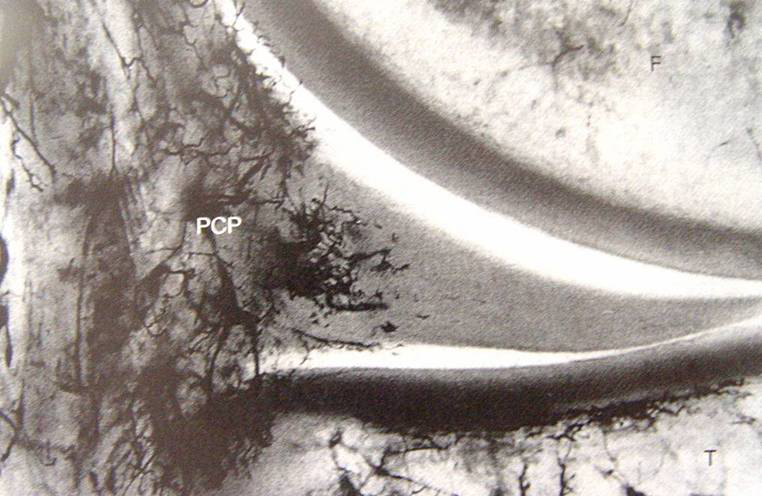

半月板血液供應

邊緣處和前后角(10-30%)